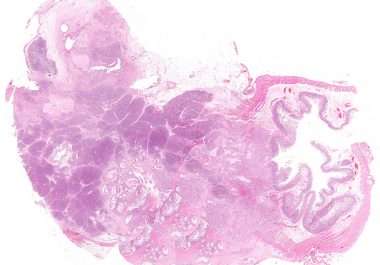

Pancreatic ductal adenocarcinoma (PDAC) is an aggressive disease with a grim prognosis. While early-stage PDAC may be removed by...